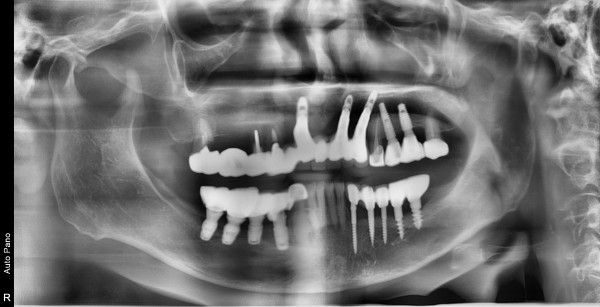

대표 상악동거상술

65세여자 우측상악 상악동거상술및임플란트식립